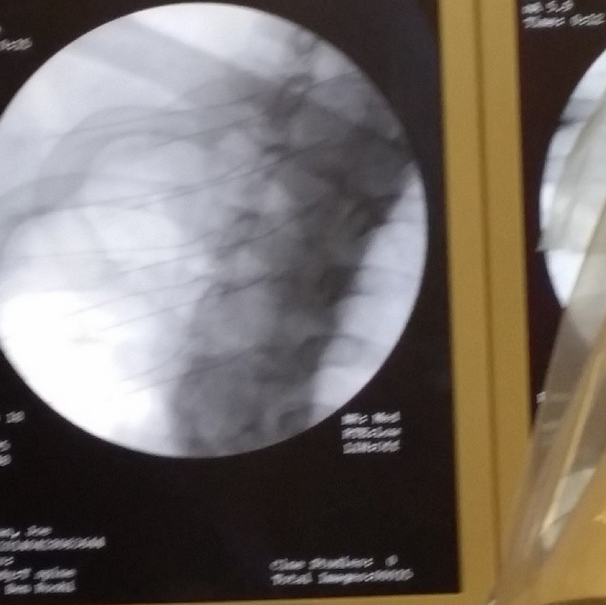

“They use an X Ray to insert the needles directly over the spine to inject the serum right onto the injured area”